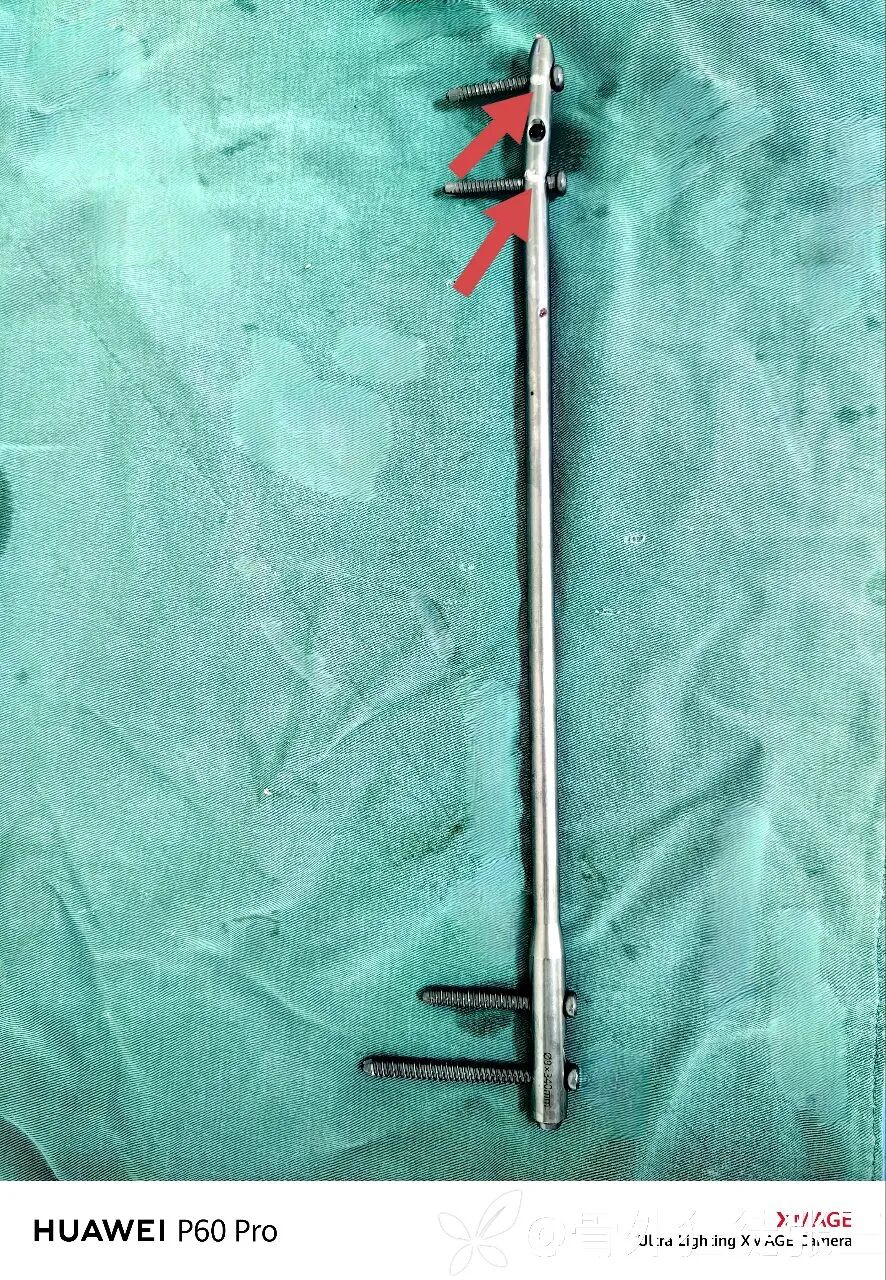

取出内固定,恢复自由身